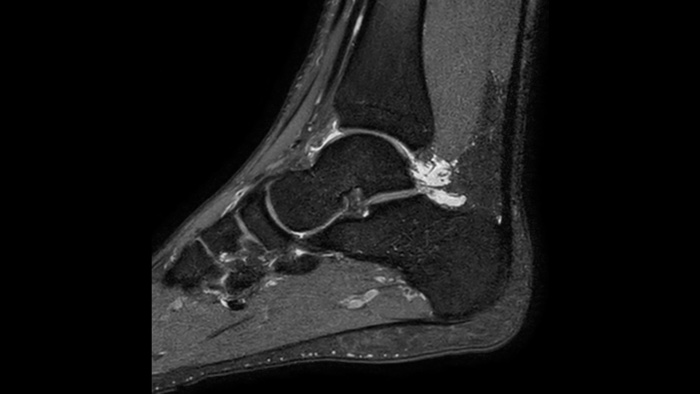

Ahora puede tenerlo todo con Ingenia Ambition. Ofrece la oportunidad de mejorar sus imágenes de resonancia magnética en todos los niveles.

Confianza diagnóstica Ofrece una resolución espacial hasta un 60% más alta en el mismo tiempo de escaneo. 4

Confianza diagnóstica Amplíe su capacidad de obtener imágenes excelentes en todas las áreas clínicas. Vea cómo se benefician sus compañeros.